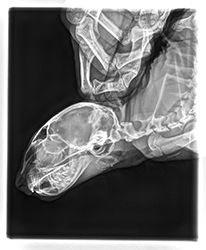

Libušce zvoní telefon, volají z veteriny od pana doktora Herynka v Černicích, že k nim majitelé přivezli tříměsíční koťátko, které neotevře tlamičku. Hledají pro něj pomoc a chtějí vědět, zda se ho ujmeme, jinak by ho museli uspat. Libunka okamžitě volá Lindě. Záměr je takový, že kocourek by měl být v dočasce v Praze a zkusíme, zda by ho odoperovali na Animal Clinic. Lindička akorát veze Medinku do nového domova za Plzeň, takže chlapečka vyzvedne cestou zpět. Leonidase přebírá s tím, že se zvládá sám najíst. Od pana doktora dostáváme zprávu a také rentgeny, které na veterině pořídili.

8.8.2023

V Animal Clinic na chlapečka bohužel nemají kapacitu, Linda musí hledat dál. Okamžitě kontaktuje naše doktory v Nuslích, přeposílá rentgeny a zprávy, které máme, prosí o radu. Z Nuslí dostává kontakt na CT na klinice na Zbraslavi; přesto se ptá, zda stačí pro tak maličké koťátko obyčejné CT, nebo zda je 3D lepší. 3D je prý obecně lepší, ale obyčejné stačí. Ještě ten večer se ale ukazuje, že Leova schopnost sám se najíst je spíš špatná až mizivá a je potřeba ho dokrmovat z lahve. Linda okamžitě sedá ke googlu a hledá 3D CT veterinární pracoviště. Jediný 3D CT skener pro zvířata je v Opavě. Linda posílá info a žádost o termín do Opavy a čeká.